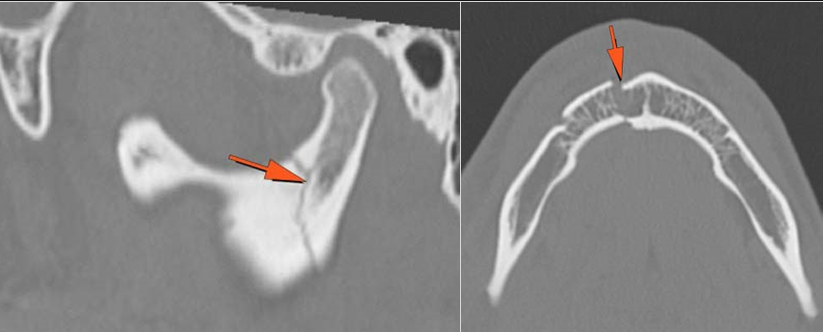

Mandible and Temporomandibular Joints

Dentition